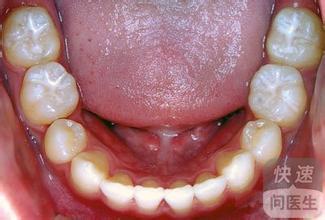

虫牙是一种常见的口腔疾病,很多人都曾经或正经历着牙齿长虫牙的痛苦。虫牙的形成是由于长期饮食、口内环境不清洁,细菌长期繁殖形成酸性环境而导致牙齿表面钙质溶解,产生菌斑、牙上石等病变,最终形成虫牙。

如果发现自己长了虫牙,要及时治疗,否则虫牙会越来越严重,甚至会引发痛苦和牙齿松动脱落等影响。下面我们介绍几种挽救虫牙牙齿的方法:

口腔卫生的重要性。保持口腔清洁,及时刷牙、使用牙线、漱口等措施,能够有效减少虫牙的发生。

洁牙治疗。定期到口腔科医院洁牙,去除牙石和菌斑,减少牙齿上的细菌数量和繁殖速度。

修复虫洞。如果虫牙已经形成,需要及时到口腔科医院进行牙齿修复,去除腐烂的牙齿组织,进行一些牙齿修复措施,例如复合树脂充填、烤瓷牙等,保留好健康的牙齿。

改善饮食结构。坚果、蔬菜、水果等富含纤维素的食物有助于增加口腔清洁度,防止牙菌斑的形成。减少粘性和含糖量高的食物的摄入,例如糖果、巧克力等,这些食物会让牙齿上的菌群得到充分的营养而不利于牙齿健康。